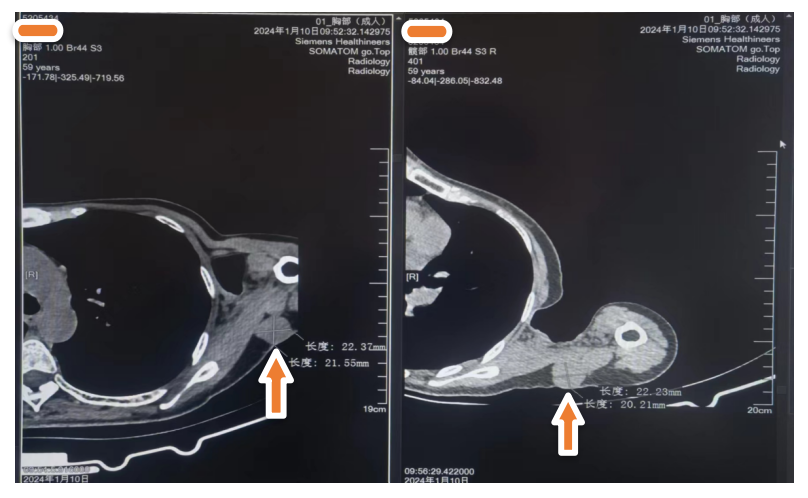

治疗3年6个月后 2024年1月10日